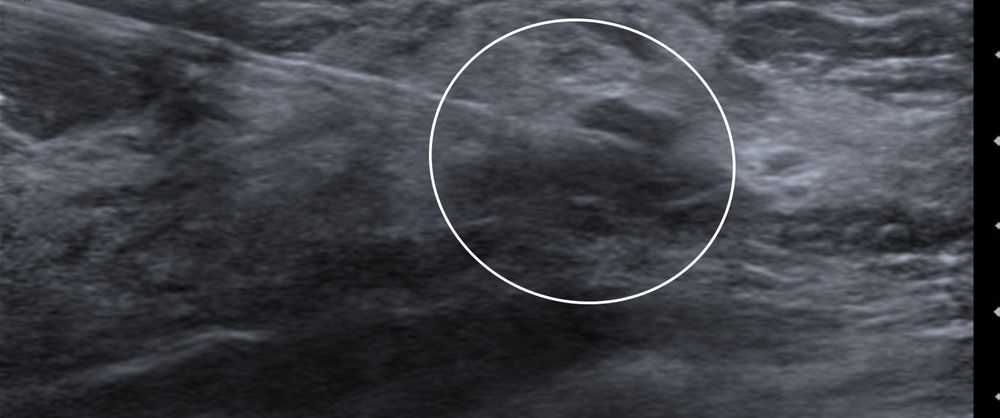

Σε περίπτωση που απαιτείται η χειρουργική αφαίρεση ενός ευρήματος που δε ψηλαφάται από το χειρουργό, τότε γίνεται η τοποθέτηση αγκίστρου σήμανσης (hook) λίγο πριν το χειρουργείο. Το άγκιστρο έχει σκοπό να καθοδηγήσει το χειρουργό για την αφαίρεση του σωστού τμήματος του μαστού, ώστε να αφαιρεθεί με ασφάλεια η ύποπτη βλάβη χωρίς να επηρεασθεί η αισθητική εικόνα του μαστού, πράγμα πολύ σπουδαίο ειδικά σε νέες γυναίκες και σε γυναίκες με μικρό μαστό.